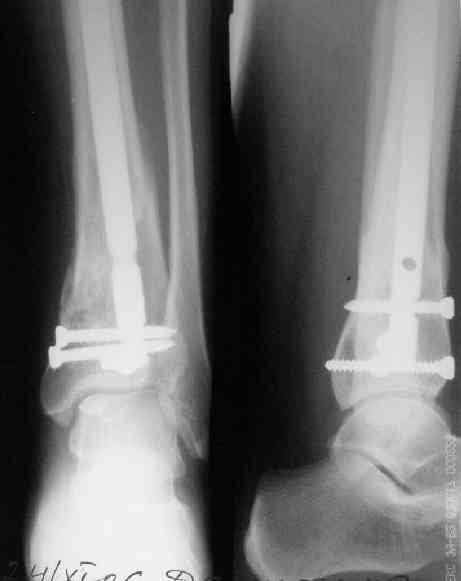

В приложении пример лечения аналогичного повреждения (плюс задний край).